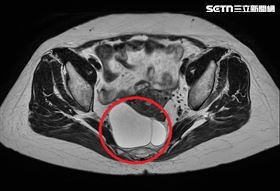

因禍得福!她車禍意外揪直腸藏10CM腫瘤

台中一名44歲張姓女子,因發生車禍送醫,安排腹部電腦...

婦出車禍反保命 意外揪出直腸長腫瘤

44歲張婦因車禍送醫安排腹部電腦斷層檢查,結果意外發...